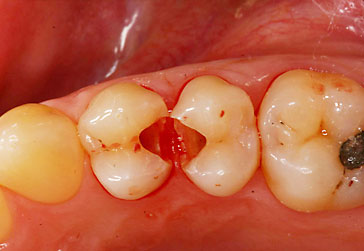

Compositerestauration

![]() |

Kunststoffrestaurationen

Zahnärztliche Kunststofffüllmaterialien eignen sich hervorragend für die substanzschonende Versorgung kleiner bis mittelgroßer Defekte am Zahn. Hinsichtlich Härte, Abriebfestigkeit und Stabilität gegenüber Flüssigkeiten (z.B. Speichel) haben sie bessere mechanische Eigenschaften wie Amalgamfüllungen. Bei ausgedehnten Defekten jedoch stoßen die Kunststofffüllungen an die Grenzen ihrer Dichtigkeit und Stabilität. In solchen Fällen ist, je nach Größe der Defekte, Einlagefüllungen wie Keramikinlays, Goldinlays oder Kronen bzw. Teilkronen den Vorrang zu geben.